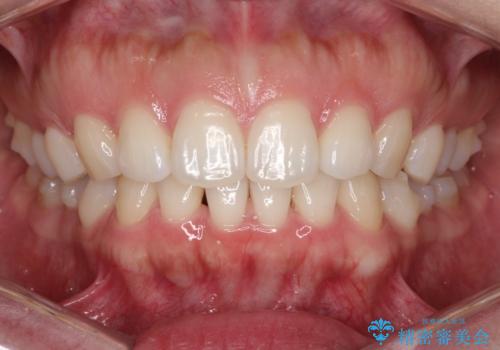

- 前歯の歯並びの改善を希望され来院された患者様です。

初診時の歯並びの状態としては、下顎前歯に及ぶの中等度のがたつき(叢生)があり、前歯が深く噛みこんでいる状態でした。

抜歯は行わず歯列弓の拡大やディスキング(歯と歯の間の隙間を作る処置)を行い叢生を改善しました。

見た目、嚙み合わせ及び、治療期間や施術内容に大変ご満足いただきました。